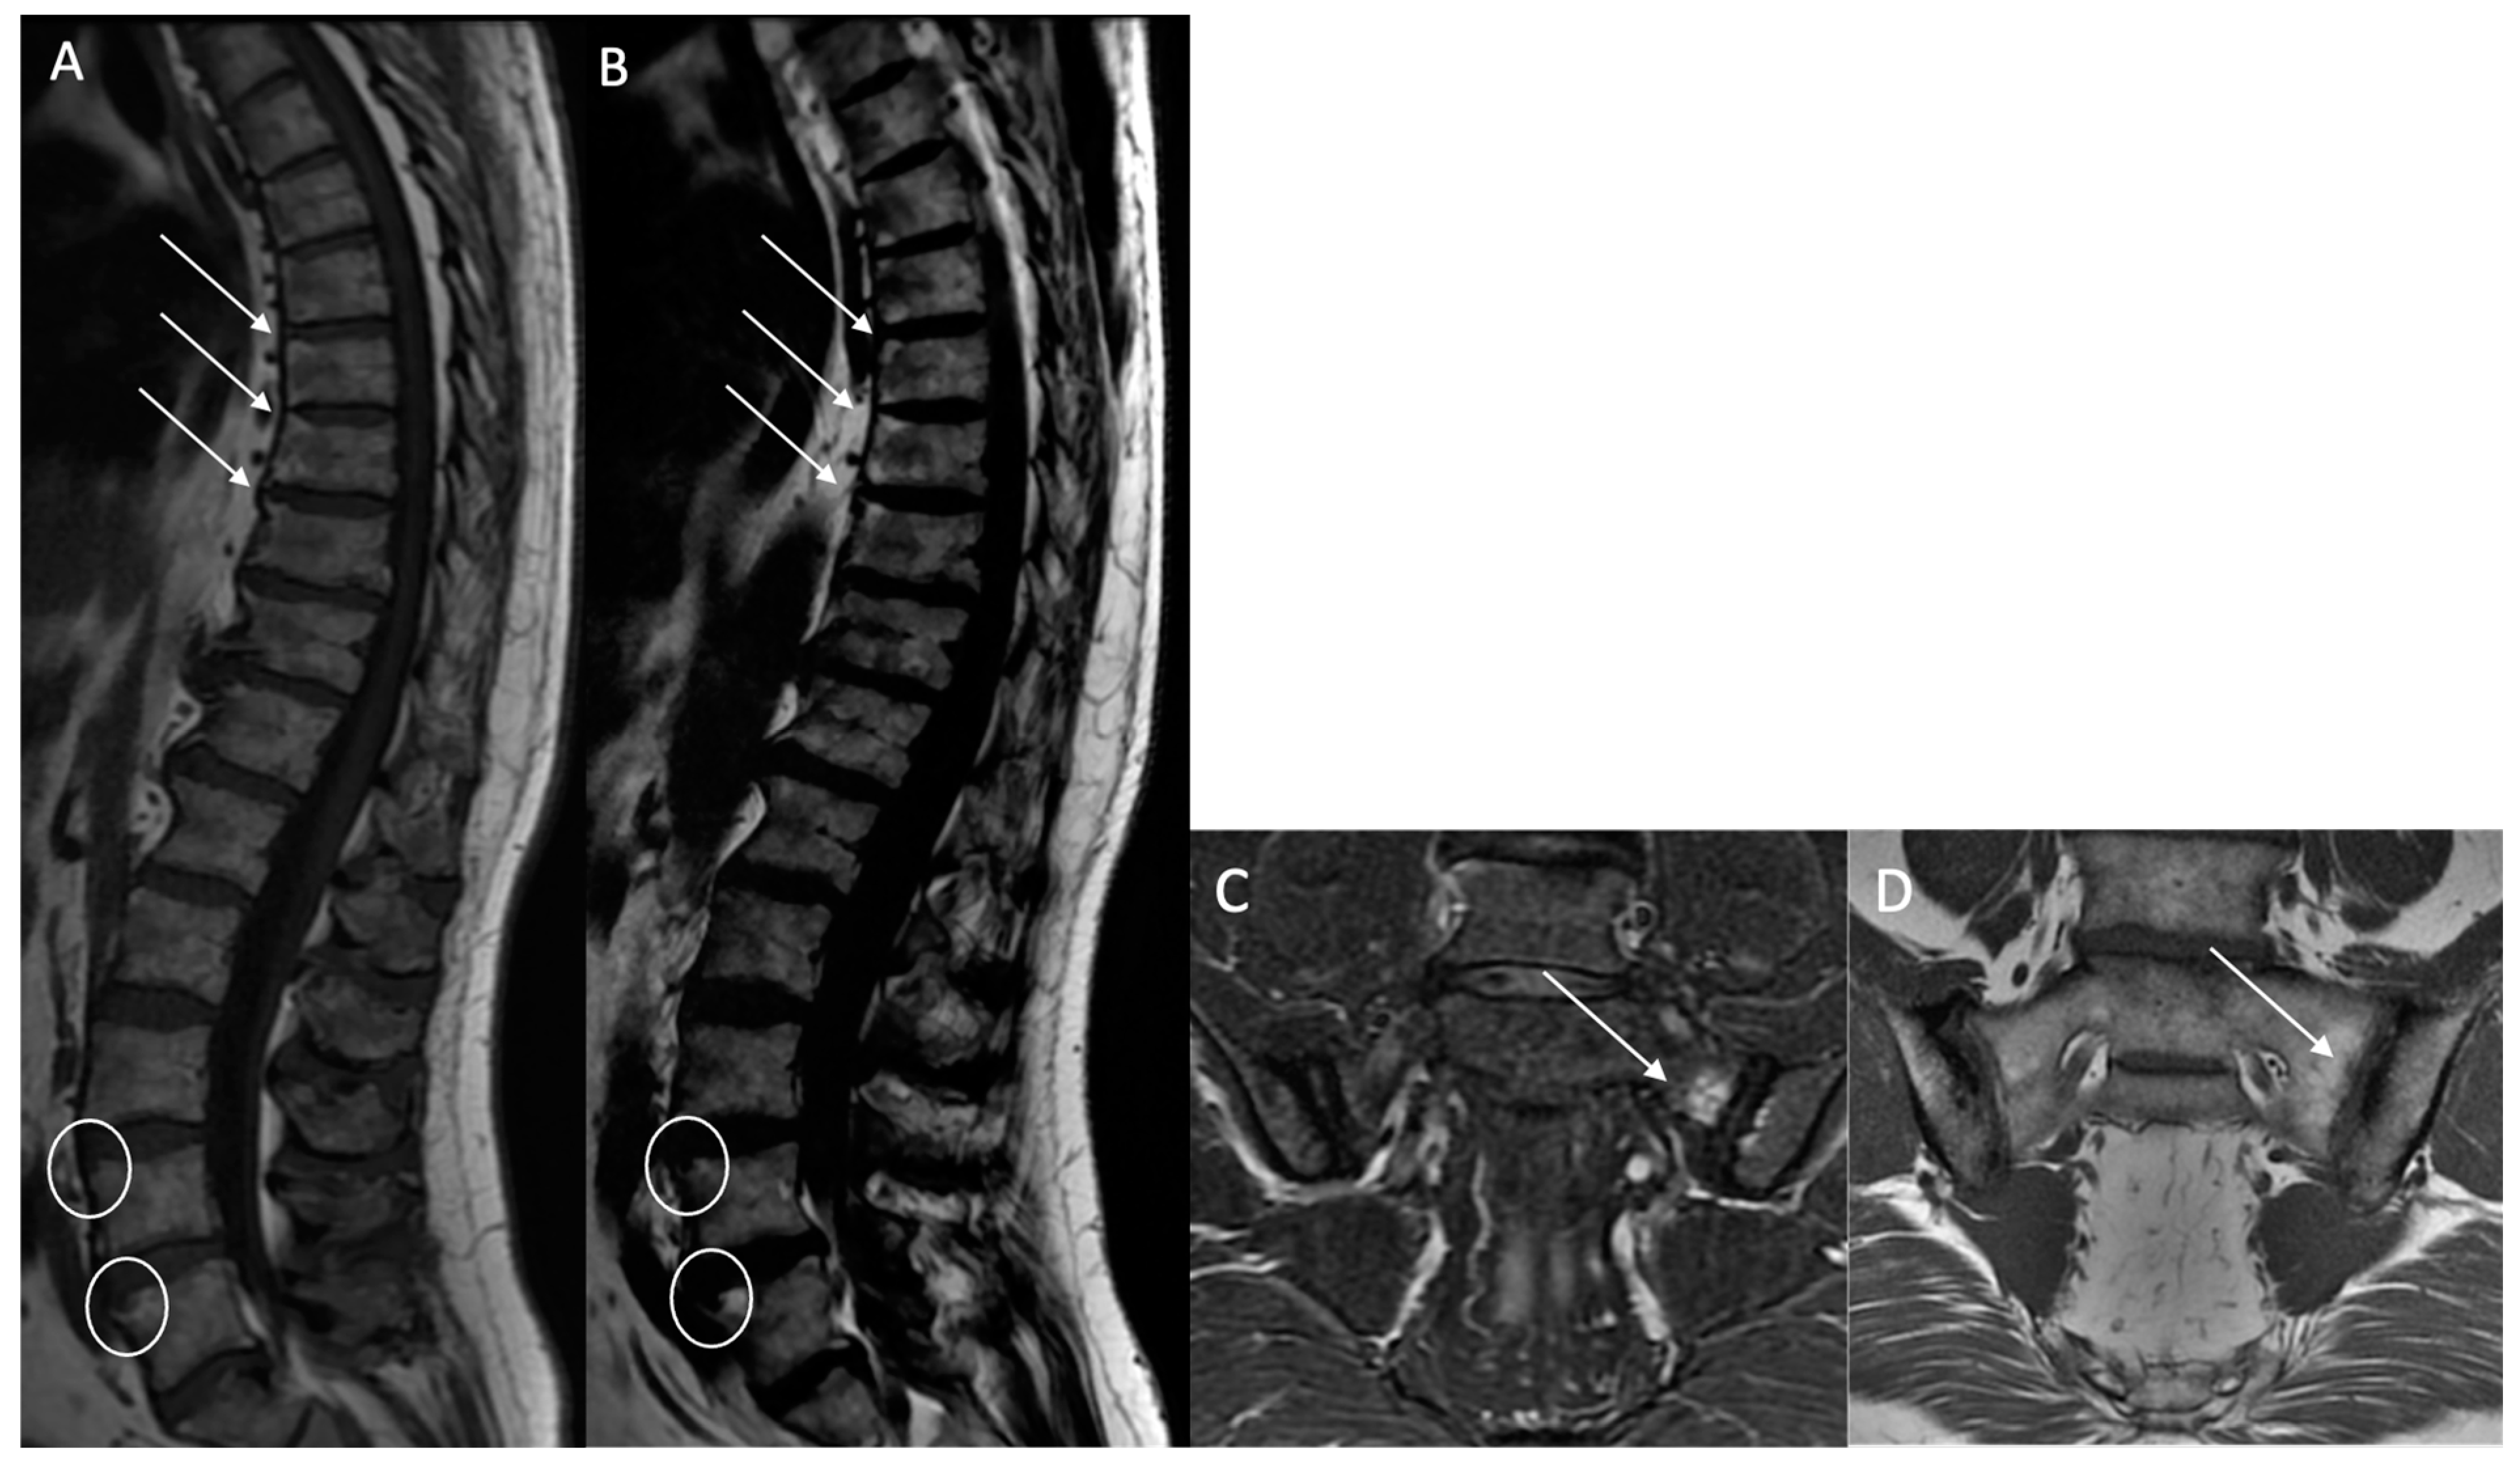

Fatty lesion (BMF): Defined as the presence of high signal intensity, similar to that of adipose tissue, on T1w MR images, or persistent fat areas on the “fat-only” Dixon FST images (Figure 2).

Figure 2. Multiple fatty lesion (BMF) changes and sacroiliac structural changes with partial ankylosis in a 44-year-old patient. A T1w sagittal sequence showing BMF localization at a longitudinal ligamentary structure enthesis (arrows) (A). A T2w Dixon (fat) image more clearly showing BMF localization (arrows). No ankylosis, sclerosis, or erosions were found (B). A T1w coronal oblique sequence of a sacroiliac joint showing periarticular fatty changes (*). A T1w coronal oblique sequence on a sacroiliac joint showing structural changes with partial ankylosis (arrrowheads). No inflammatory changes were noted (C,D).